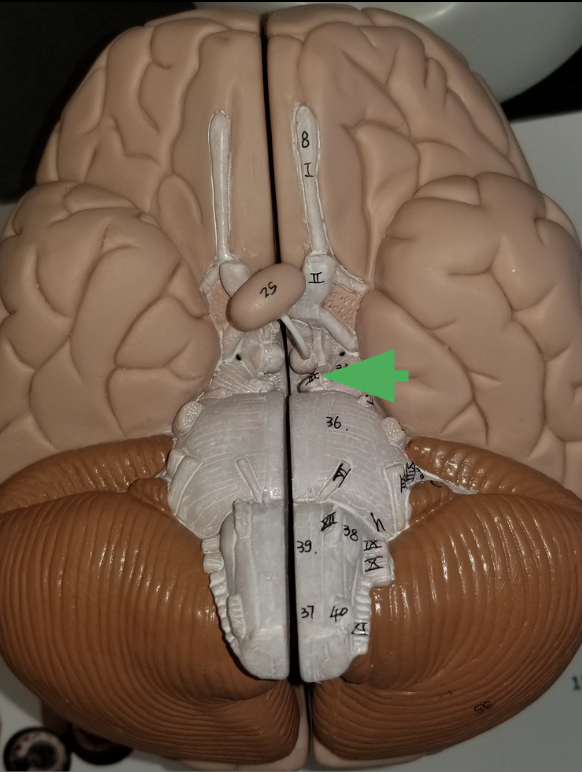

What is the arrow pointing at?

Oculomotor nerve

What is the arrow indicating?

Trigeminal nerve (cranial nerve 5 /V )

What does the trigeminal nerve do?

Carries sensory information from the face

Carries motor commands to chewing muscles